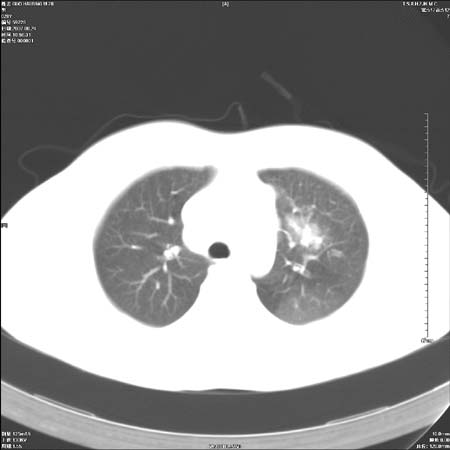

本例倾向周围型肺癌

鉴别:中央型肺癌-肿块那么明显一般合并节段肺不张或阻塞性炎症。

本例肿块边缘外侧可见左上叶各段支气管。

左侧肺门区见一块状病灶可见分叶,纵隔内及左肺门见肿大淋巴结,应该是周围型肺癌而不是中心型肺癌,原因有以下2点,1未见阻塞肺气肿和阻塞性炎症,这么大肿块如果是中心型肺癌就是未分化型或小细胞型肺癌不出现阻塞性肺不张也应该有阻塞炎症或阻塞性肺气肿,2如果是中心型肺癌临床出现最早的症状是咳嗽(此时可无任何异常影象),而此人这么大肿块只有背部隐痛是体检才发现无法解释.